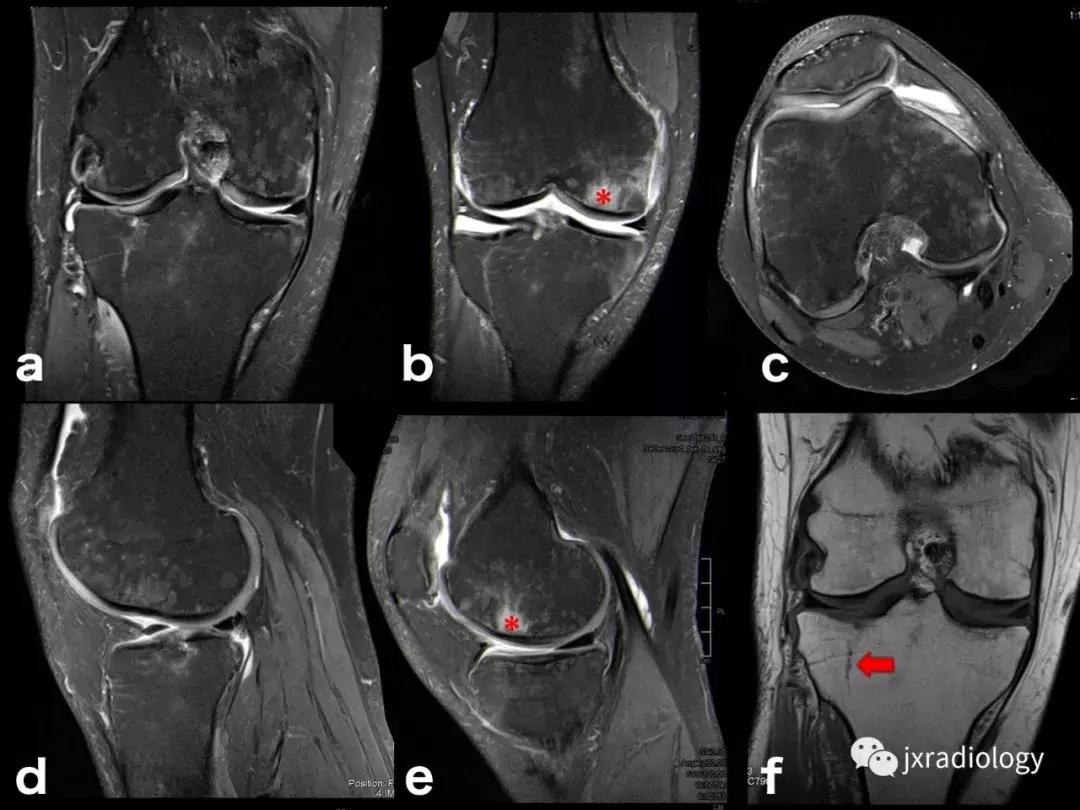

图8:创伤性骨髓水肿,髌骨脱位的典型病例:青年人,髌骨一过性脱位和挫伤的横断面(a,b,c),冠状面(d,e)和矢状面(f)的PD-FS-WI图像 :股骨外侧髁的前外侧和髌骨下内侧的故事水肿。 对于进行运动的青少年或年轻人来说,在弯曲时需要膝盖扭转运动的情况更为常见。 如该患者患有髌骨骨软骨损伤(*)和内侧髌股韧带(MPFL)撕裂(箭头)。